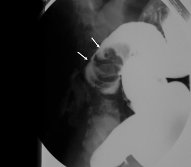

• 바륨 대장조영술: 신경절이 없는 좁아진 부위(narrow segment)와 그 위로 확장된 부위(dilated segment)가 관찰됨. (transition zone 확인)